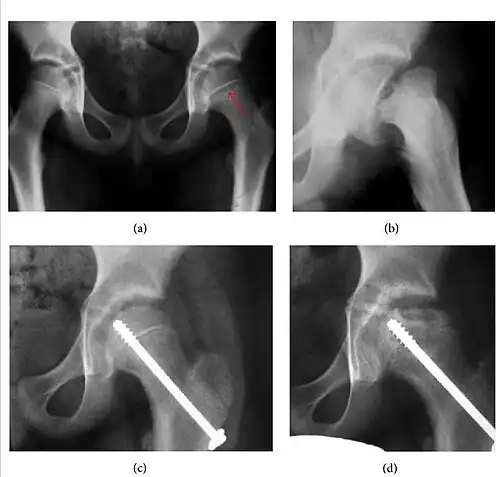

Figure 1.

-

Radiography in normal hip -

X-ray in pincer impingement type of hip dysplasia -

X-ray of cam -

Hip in osteoarthritis -

Septic arthritis

Slipped capital femoral epiphyses (SCFE) usually affect 11- to 14-year-old adolescents (Figure 4). Radiographs may show widening and irregularity of the physis and posterior inferior displacement of the capital femoral epiphysis. On the AP view Klein’s line, tangent to the lateral aspect of the femoral neck, does not intersect the femoral head indicating that it is displaced. SCFE may compromise the blood supply to the femoral head and cause avascular necrosis, mainly when there is instability between the fragments.[1]

Figure 4: (a) X-ray of a 10-year-old child with left hip pain. It was considered normal at emergency despite the widening of the left physis (arrow). Two weeks later epiphysiolysis was evident (b). Despite appropriate surgical reduction (c) osteonecrosis developed and femoral head collapsed 1 month later (d).[1]